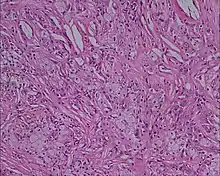

Xanthelasma

Histology picture of xanthoma showing lipid-laden foam cells with large areas of cholesterol clefts, 10 × magnification, eosin and hematoxylin stain[1]